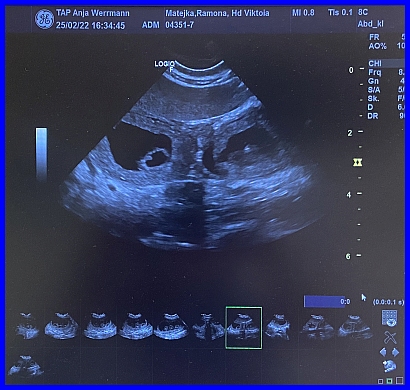

Da sind sie, Zwillinge :-) die ersten Babys!

Hier ist ganz eindeutig eine gefüllte Fruchtblase zu erkennen, links ist das kleine Köpfchen und die "Kugel" in der Mitte der Fruchtblase, ist der Körper des Fötus.

Es ist der 29. Tag der Trächtigkeit. Viktoria fand es ziemlich blöd auf dem Tisch, das sieht man ihr auch deutlich an.